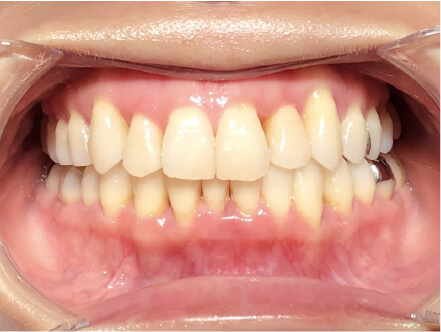

叢生の症例

17歳

女性

カウンセリング・診断結果

治療内容・方法

全額アライナー矯正

術後の経過・現在の様子

クリアライナー使用

痛み・歯根吸収・歯肉退縮・虫歯・後戻り

費用・治療期間

715,000円、2年10ヶ月